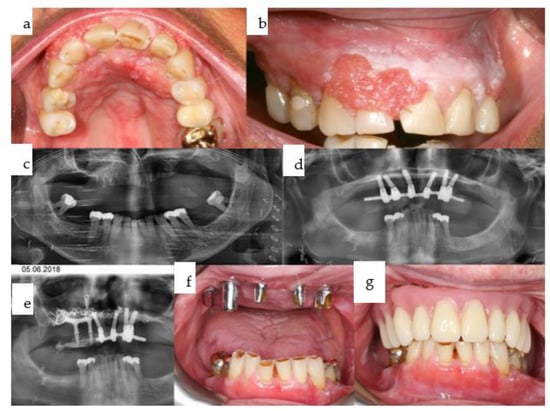

Figure 19. (ac): The patient underwent primary resection and bridging of the remaining mandibular segments, along with intra- and extraoral soft tissue flap reconstruction (a). The second-stage surgery involved the microvascular osteocutaneous fibular flap for bony mandibular reconstruction (b), followed by dental rehabilitation based on six conventional dental implants in the maxilla and a customized subperiosteal implant in the mandible (c).